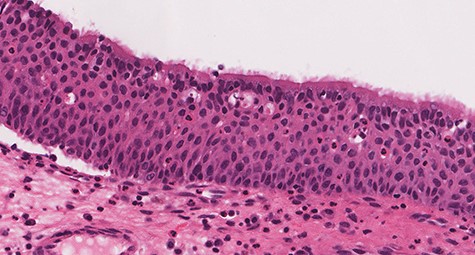

Histologic sections show an endophytic (inverted) pattern that grows downward into the underlying stroma (Fig. 4). The epithelium consists of hyperplastic squamous epithelium (Fig. 5) and ciliated columnar cells admixed with scattered mucocyets (goblet cells) (Fig. 6). The cells have a bland appearance and uniform small nuclei. No cytologic atypia, increased mitotic activity or necrosis seen. Mixed inflammatory cells are dispersed within the epithelium and stroma.